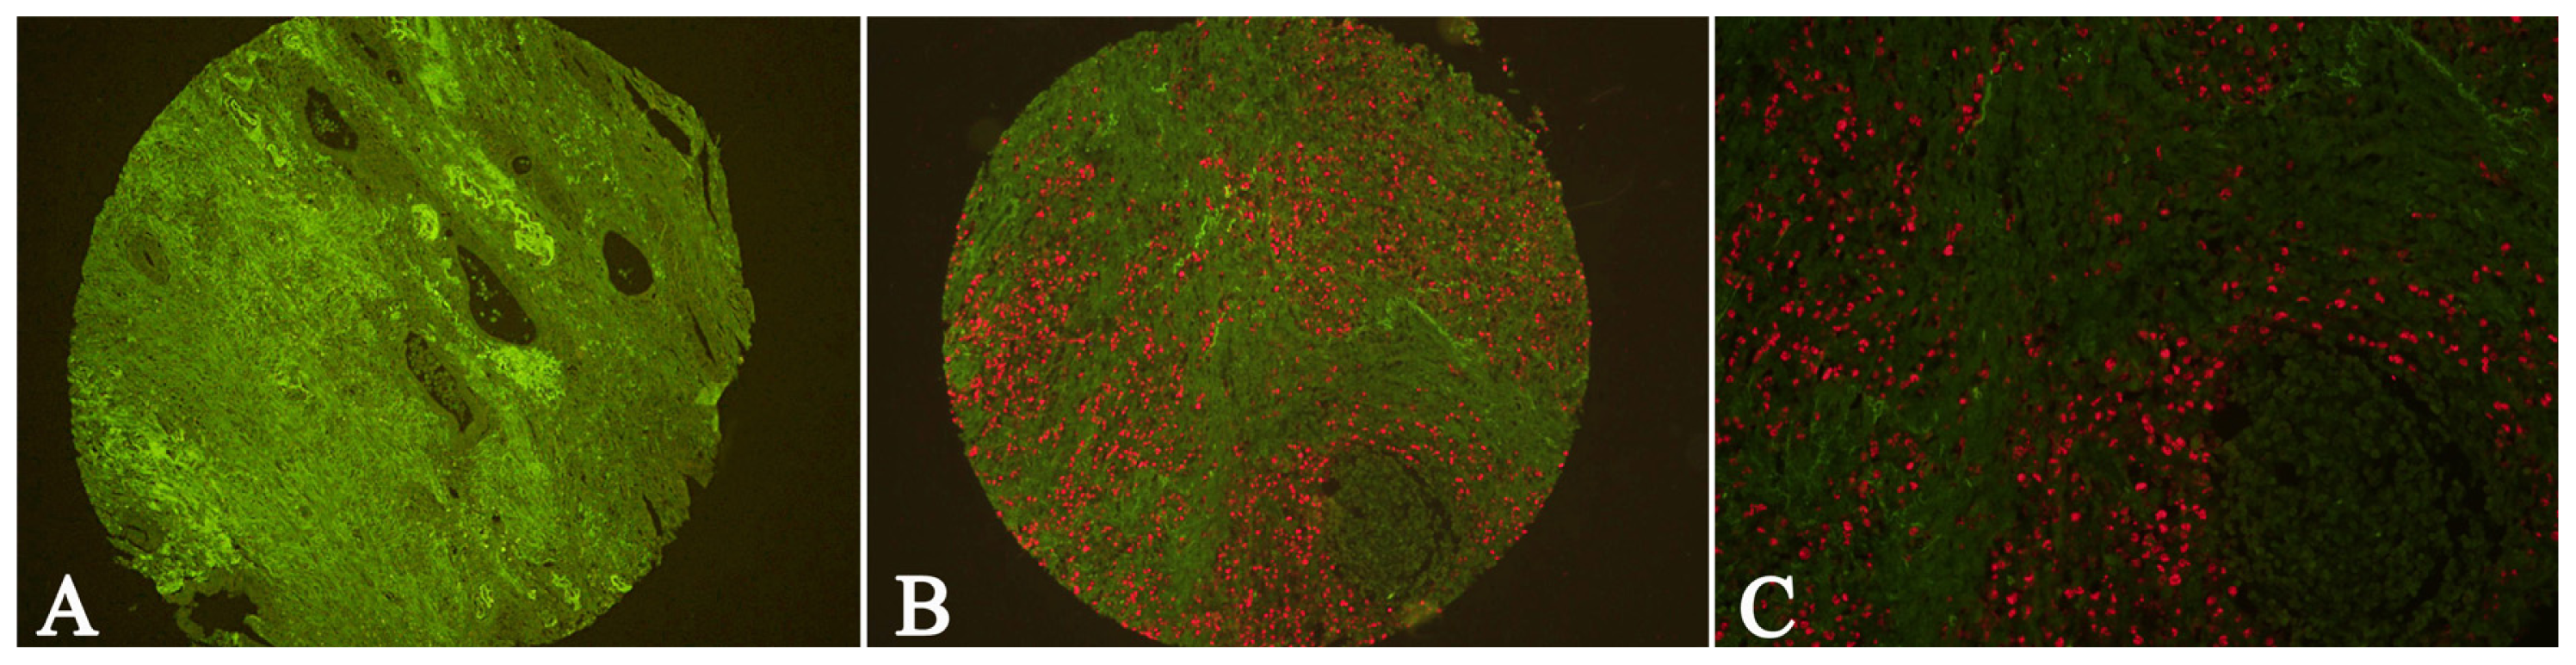

3.4. QDs-Based Double Immunofluorescence Labeling

- Peng, C.W.; Liu, X.L.; Chen, C.; Liu, X.; Yang, X.Q.; Pang, D.W.; Zhu, X.B.; Li, Y. Patterns of cancer invasion revealed by QDs-based quantitative multiplexed imaging of tumor microenvironment. Biomaterials 2011, 32, 2907–2917. [Google Scholar]

- Peng, C.W.; Tian, Q.; Yang, G.F.; Fang, M.; Zhang, Z.L.; Peng, J.; Li, Y.; Pang, D.W. Quantum-dots based simultaneous detection of multiple biomarkers of tumor stromal features to predict clinical outcomes in gastric cancer. Biomaterials 2012, 33, 5742–5752. [Google Scholar]